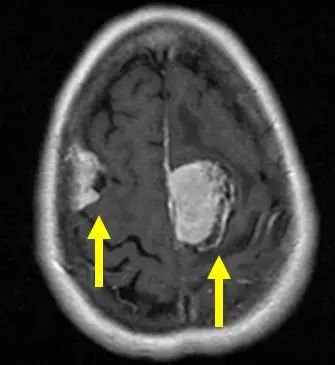

辐射诱发的脑膜瘤,通常源于低剂量辐射导致的头皮癣或高剂量辐射导致的血液或头颈部癌症,其往往为高分级、多灶性病变。从接受辐射到肿瘤发生之间存在几十年的潜伏期。下图为一例38岁的女性患者的MRI图像,她在头颅局部放射治疗急性淋巴细胞白血病后32年发病。轴位单层面图像显示了三个脑膜瘤中的两个。较大病变附着到大脑镰——一种将大脑分为左右半球的硬脑膜结构,较小肿瘤则沿右额叶凸出生长。大脑镰旁脑膜瘤和凸面脑膜瘤占全部脑膜瘤的近一半。